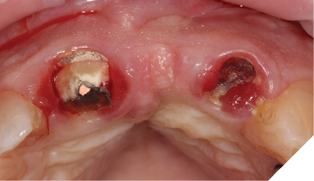

Radiographic examination shows the upper left lateral incisor tooth has decayed through and through and the upper right central incisor tooth is heavily root treated and filled (Figs. 1-2).

The existing metal ceramic bridgework was thick and bulky, but the patient was used to it. The patient also didn’t have any pain or discomfort yet from the slightly loose bridge or dental caries. The patient was most concerned the bridge would suddenly come out and would have a space (Figs. 3-4).